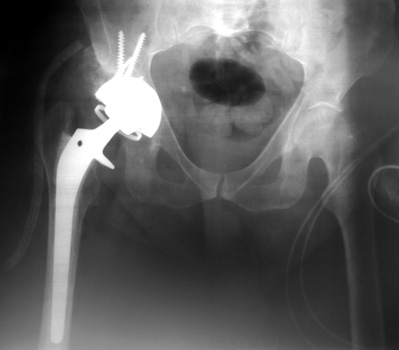

Dislocated total hip replacement